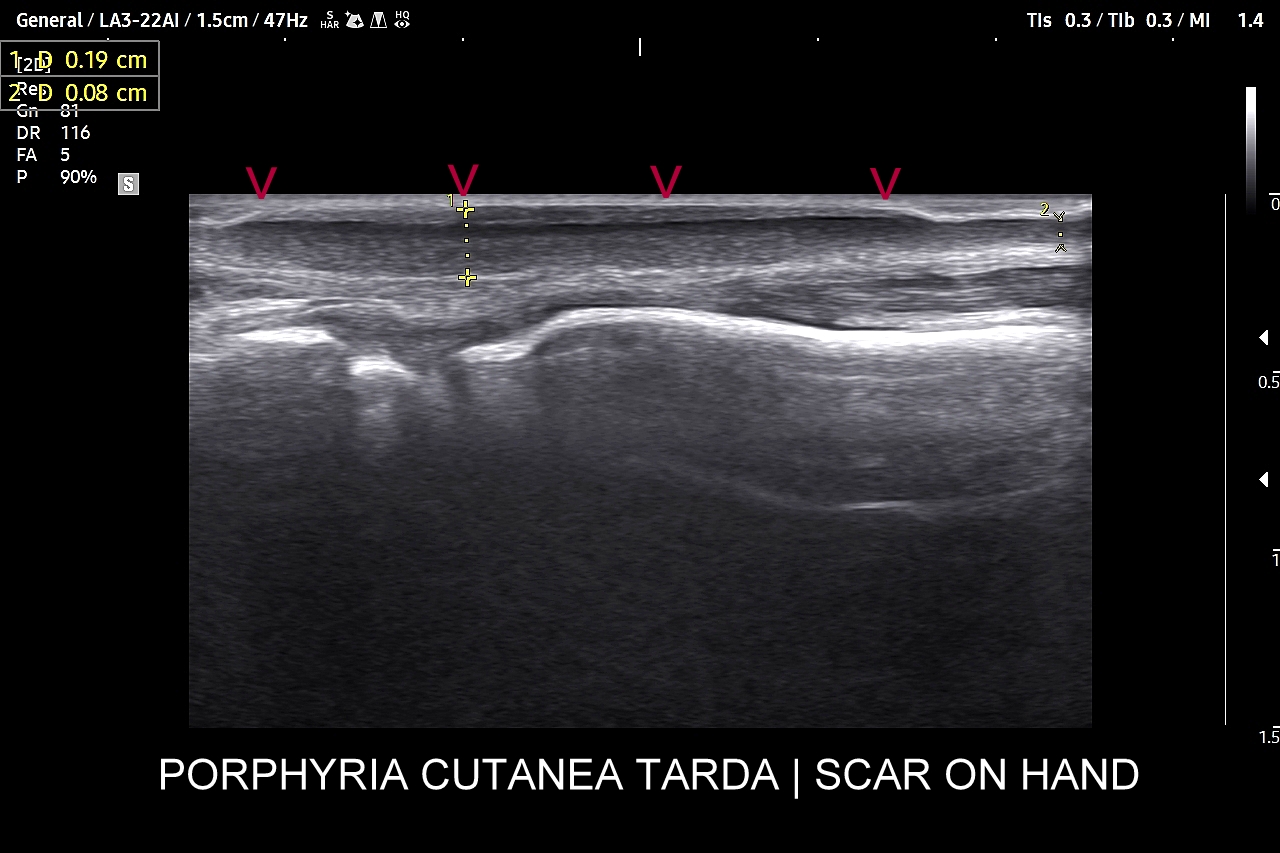

Badanie USG skóry i powłok jest metodą diagnostyczną, która swoją czułością oraz dokładnością przewyższa w ocenie patologii powłok badanie rezonansem magnetycznym. W obrębie powłok ciała w badaniu USG najczęściej rozpoznaje się różnorodne guzy oraz stany zapalne. Wśród guzów dominują łagodne tłuszczaki, kaszaki i torbiele inkluzyjne, a także przepukliny. U młodszych pacjentów często wykrywa się naczyniaki. Rzadziej spotkane są guzy złośliwe jak mięsaki, czy przerzuty nowotworowe. W pracowni USG dr Szczepańskiego poza wizualną oceną guzów powłok przeprowadzana jest ich ocena biologii w kontekście cech złośliwości i oceny przewidywalnego tempa wzrostu.

W obrębie schorzeń zapalnych typowo wykrywa się ropnie, przetoki, infekcyjne zapalenia tkanki podskórnej (np. róża), rzadziej głębsze infekcje powięzi i zagrażające życiu infekcje podpowięziowe. Badanie USG powłok jest bardzo przydatne w chirurgii, gdyż dzięki niemu można szybko i sprawnie zdiagnozować powikłania chirurgiczne takie jak krwiaki, zacieki, ropnie, ciała obce, przepukliny brzuszne, a także można oceniać i monitorować gojenie się blizny, czy położenie drenów. USG pomaga także diagnozować endometriozę w powłokach brzucha i w bliznach po cięciu cesarskim.